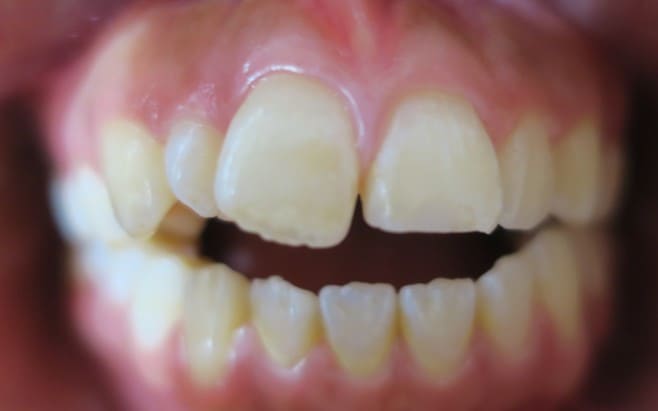

● 先天性の萌出方向異常を部分矯正で治療

藤沢デンタルオフィスの虫歯や破折で先天性の萌出方向異常を部分矯正で治療

01

02

03

04

05

06